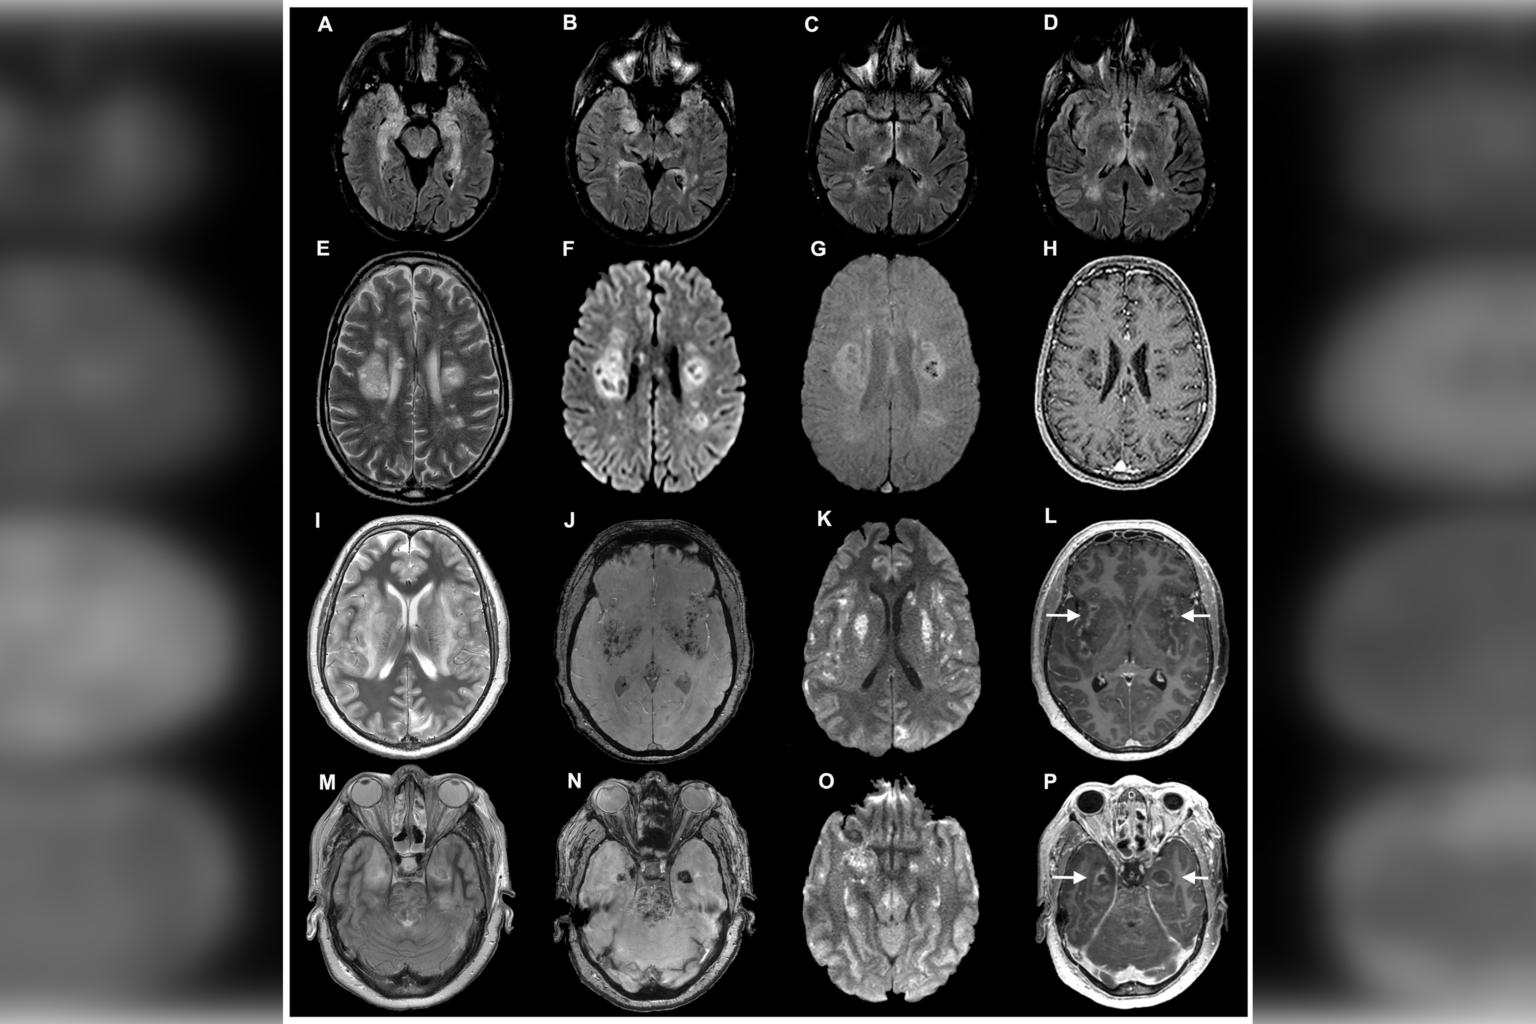

Finally, they examined the brains of three patients who died from severe Covid-19 related complications, finding evidence of the virus in all to varying degrees.

Intriguingly, the infected regions did not show signs of having been infiltrated by immune cells, such as T-cells, which rush to the site of other viruses like Zika or herpes to kill the infected cells.

This could hint that the overloaded immune response known as cytokine storm which is responsible for much of the damage seen in the lungs of Covid-19 patients might not be the main cause of neurological symptoms.